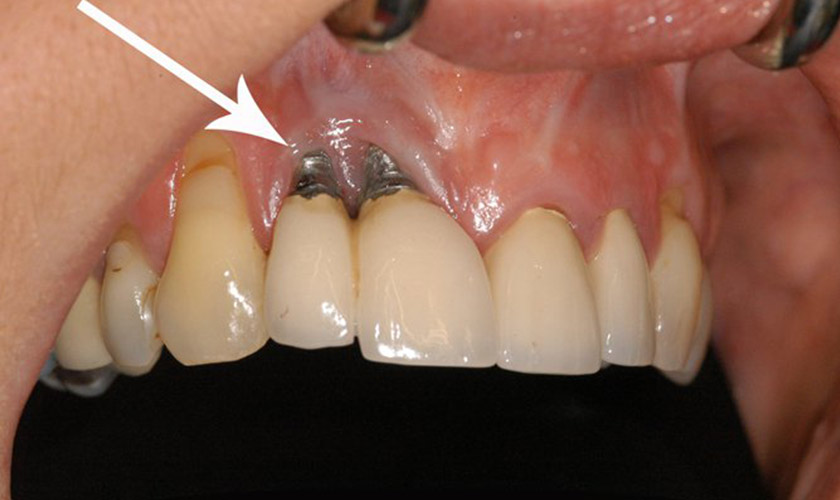

❌ 1. Sử dụng trụ Implant kém chất lượng

Các cơ sở giá rẻ thường dùng trụ Implant không rõ nguồn gốc, không có chứng nhận kiểm định y tế.

Hậu quả:

- Trụ không tích hợp với xương, gây lỏng lẻo, phải nhổ bỏ.

- Viêm nhiễm mô quanh trụ, dẫn đến tiêu xương hàm.

- Dị ứng với kim loại kém chất lượng, gây tổn thương nướu nghiêm trọng.

Ca bệnh 1 – Viêm quanh trụ do trụ giả

Khách hàng 52 tuổi, từng trồng Implant tại một phòng khám không giấy phép với chi phí 4 triệu/trụ. Sau 2 tháng, vùng cắm trụ sưng đỏ, rỉ mủ. Sau khi kiểm tra tại Nha khoa Ngọc Tuấn, kết luận: trụ không tích hợp, vùng xương bị tiêu, phải phẫu thuật loại bỏ trụ và điều trị lại.